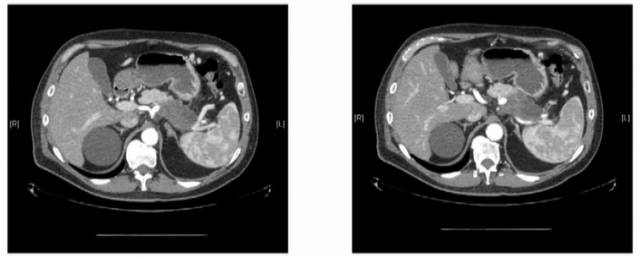

通过胰腺癌CT血管造影增强图像可以看到,胰体尾部的肿块是在局部,但是侵犯到周围血管,因此认为是局部进展期胰腺癌。